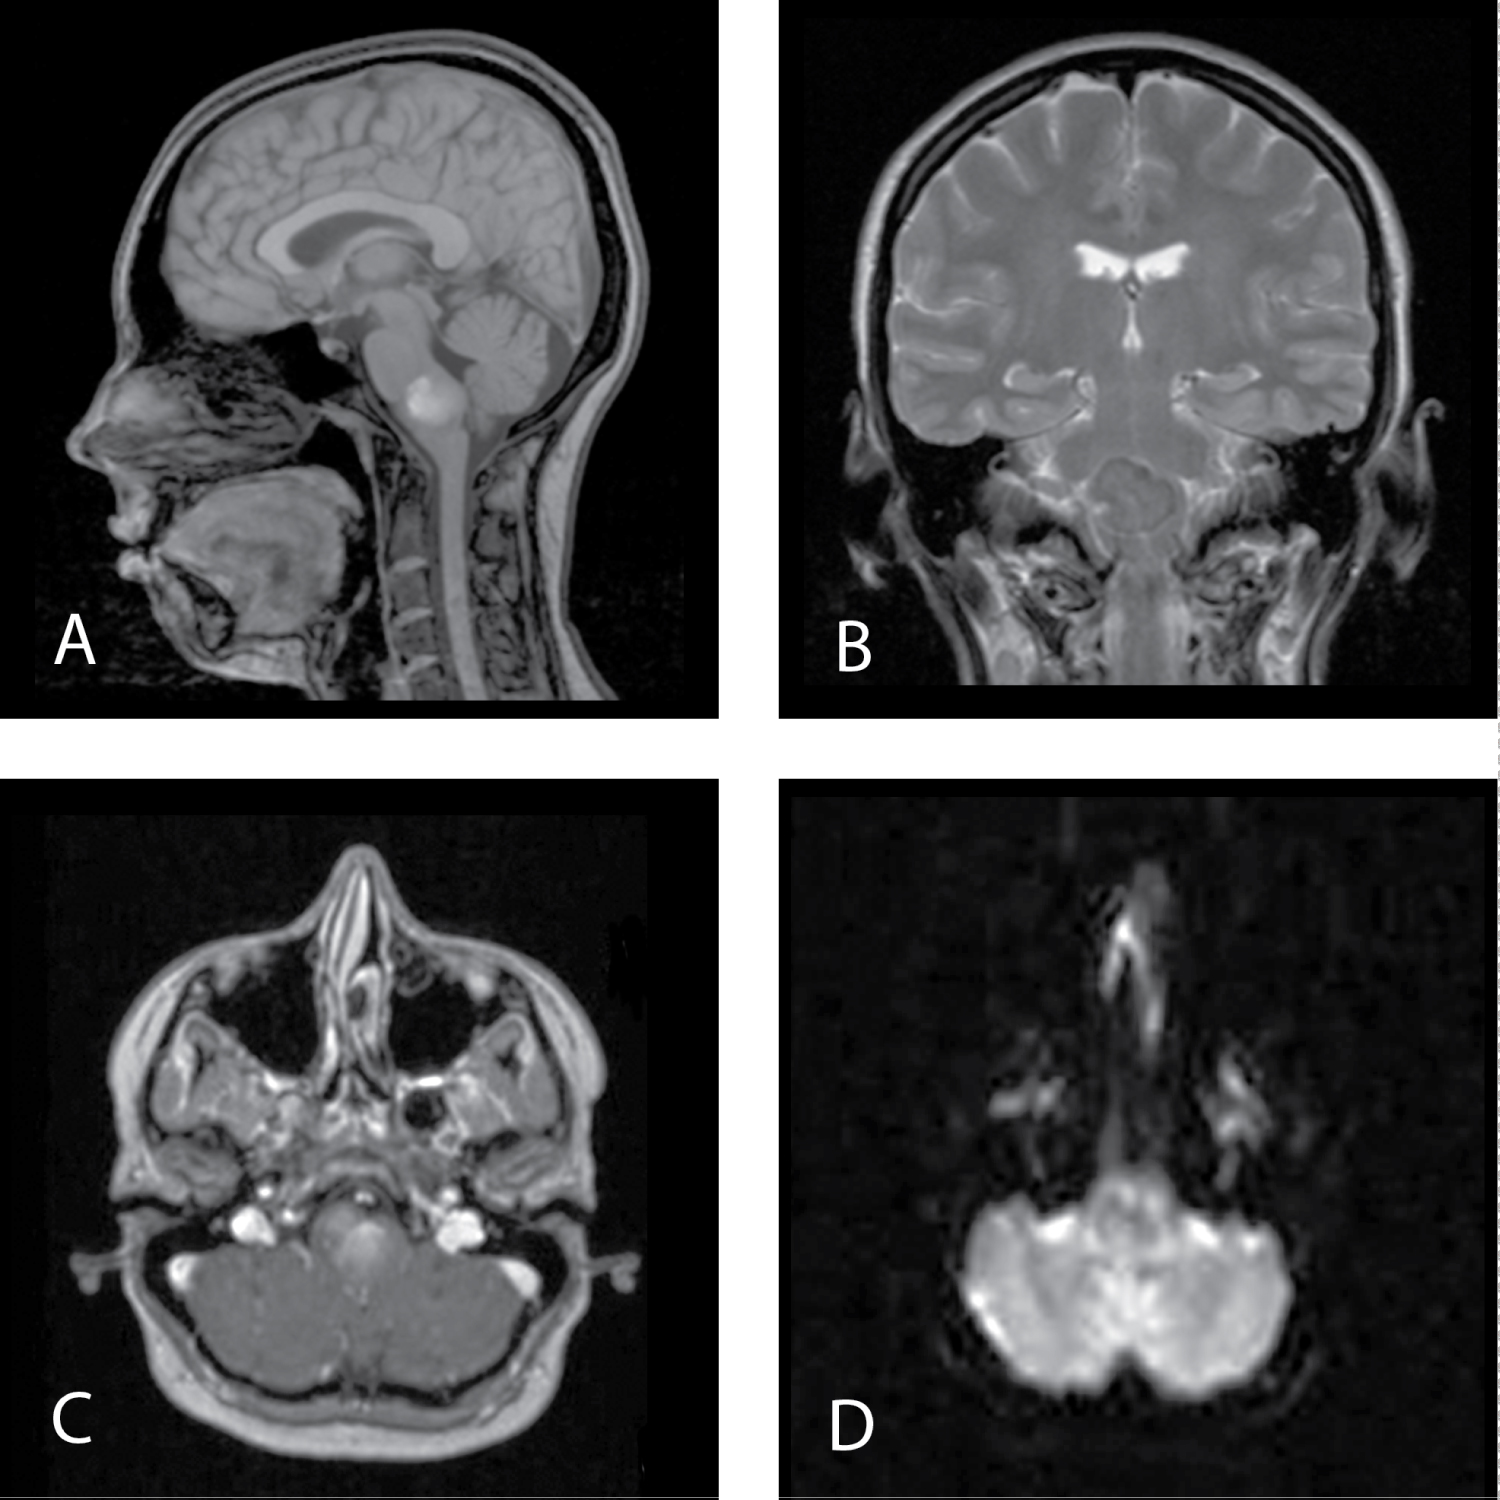

The MRI of the brain showed a well-defined lesion centered in the medulla. This lesion was homogeneously hypointense on T2-weighted images and heterogeneously hypointense on T1-weighted images and demonstrated no solid enhancing components. It was also heterogeneous lyhypo intense on DWI. PET-CT did not reveal metabolic activity in this lesion (Figure 1).

Figure 1: MRI before first surgery. A) MRI Т1 sagittal view; B) MRI Т2 frontal view; C) MRI T1 + contrast, axial view; D) MRI DWI. View Figure 1

MRI examination is a method of choice in the diagnostic algorithm of NC but its characteristics can be variable. It shows well-demarcated lesions iso- or tightly hypointense in T1 and hyperintense in T2-weighted sequences and FLAIR [5,6,8,17,18]. NCs usually demonstrate no contrast enhancement but Prasad, et al. reported mild posterior rim enhancement that can be explained by chronic inflammatory changes due to repeated cyst rupture in their view [19]. In our case MRI characteristics were not typical. Before the first the surgery lesion was heterogeneously hyperintense on T1-weighted imagesand homogeneously hypointense on T2-weighted images (Figure 1). Before second surgery MRI characteristics have changed. It was hyperintense in T2 and sites of hyperintesity in T1 were less pronounced than before the first surgery (Figure 2) that is most likely for NCs. Such change of signal can be explained by high concentration in liquid cyst cavity. It led to heterogeneously hyperintense on T1-weighted images and homogeneously hypointense on T2-weighted images before first operation.